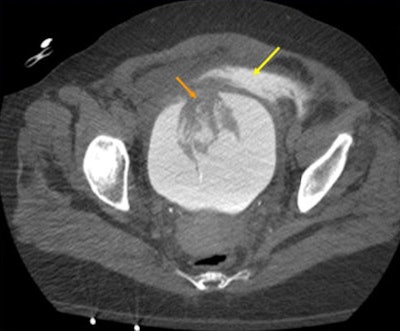

- Visceral injury, including the liver, bowel, kidney, bladder, pancreas, spleen, and adrenal glands

- Vascular injury, including aneurysm, pseudoaneurysm, laceration, hematoma, and active extravasation of any major vessel

- Intraperitoneal simple fluid, including dense intraperitoneal fluid, retroperitoneal fluid, and hematoma

- Miscellaneous findings of the mesentery and diaphragm, and anterior abdominal wall hematoma